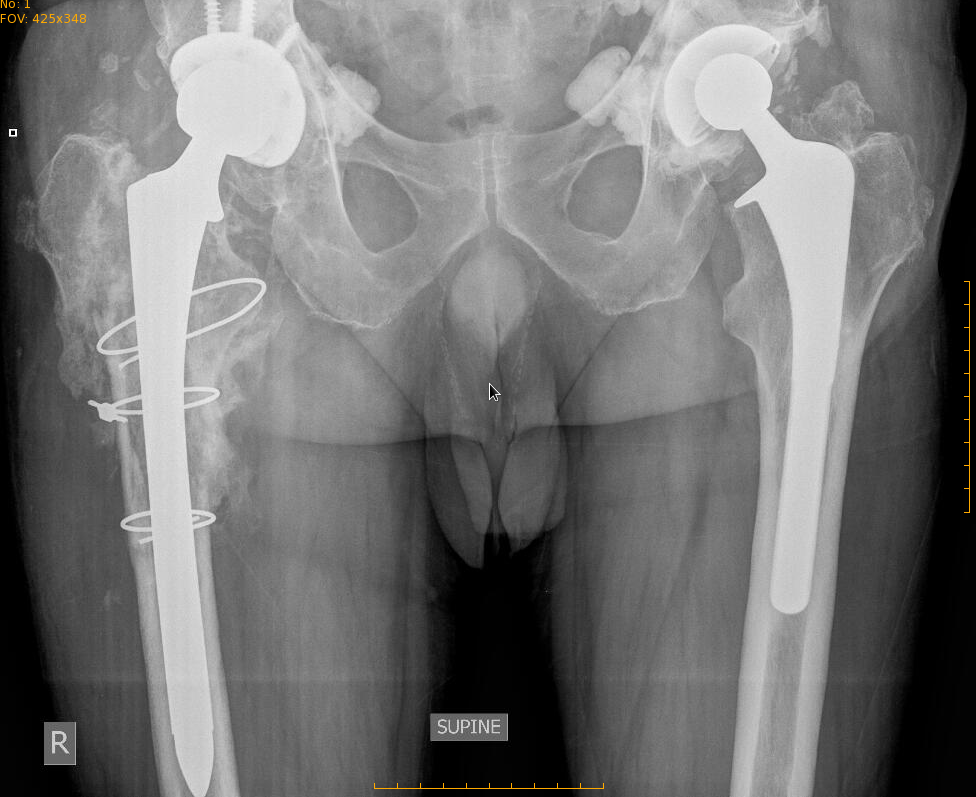

This particular hip prosthesis had functioned well for more than 20 years before it started failing. The patient started feeling severe pains, more intense and more frequent with time.

Xrays show an old style cement job, a failing prosthesis, with osteolysis, debonding.

Revision of this type of prosthesis requires removal of the old hardware, including removal of the old cement from inside the femur. In order to do this, an extended trochanteric osteotomy is necessary. This is a procedure whereby the femur bone is cut with a saw lengthwise, and then the canal is opened and scraped. The bone is afterwards repaired with circular wires.

A new prosthesis is then inserted.

This is what the revised prosthesis looks like: